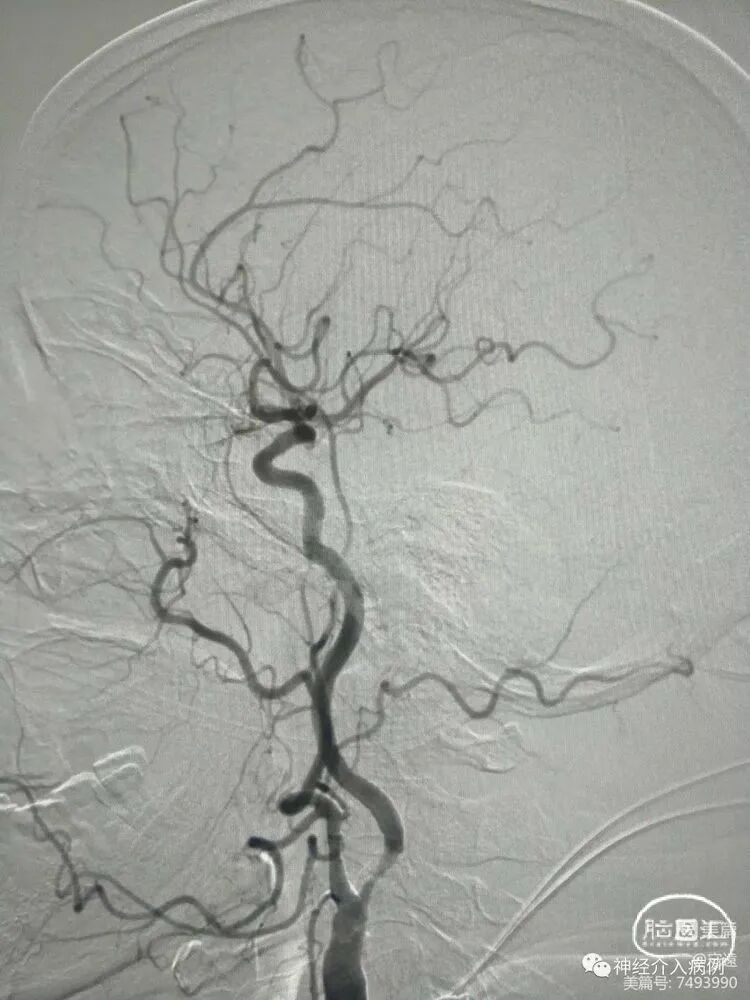

无症状性左侧颈内动脉起始段重度狭窄支架置入术(预扩张+锥形自膨式支架置入)

DSA:左侧颈内动脉起始段重度狭窄性钙化斑块,无前后交通动脉开放。